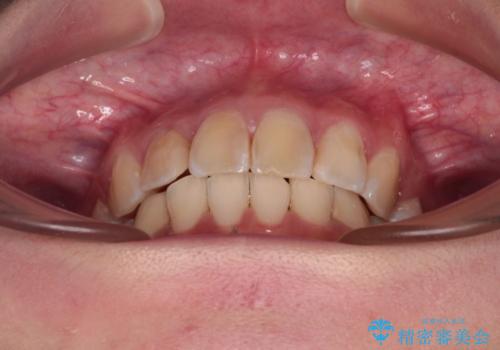

デコボコと深い咬み合わせ ワイヤー装置での抜歯矯正

- 内側に倒れ込んだ歯や下の前歯が隠れてしまうほどの咬み合わせを改善したいとのことで来院された患者様です。

下顎の叢生を解消するために抜歯が必要であり、奥歯の咬み合わせや口元の印象から、上顎も同様に抜歯と判断し、上下左右の第1小臼歯4本抜歯してワイヤー装置にて矯正治療を行うこととしました。